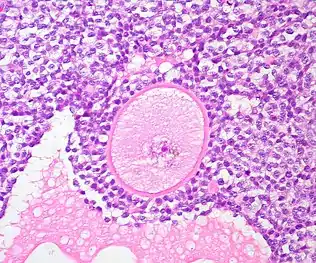

A common source of ovarian tissue used comes from tissue excised from the patient prior to cancer treatment, which is then cryopreserved.[7] The tissue is then cultured to activate the primordial follicles and allow them to develop.[2] To isolate the follicles, a combination of enzymatic and mechanical tissue digestion has shown to be the most effective method to yield a high quantity of follicles whilst maintaining their quality.[8] The enzymes used, liberase DH and DNase, are produced by good manufacturing practice (GMP) to fully comply with GMP guidelines to ensure future application to patients. The enzymatic digestion process is inactivated every 30 minutes and the suspension is filtered to allow fully isolated follicles to be removed and reduce unnecessary enzyme exposure which may lead to damage of their basement membrane and their death.[8]

The isolated follicles are then encapsulated within a 3D matrix and cultured for up to 4 weeks.[7] The material used has to meet biosafety and clinically compatible standards, such as adequate protection and support of the follicles and adaptability to human body temperature, if artificial ovaries are to be transplanted into a patient.[5] Potential materials are divided into synthetic polymers and natural polymers.[8] Synthetic polymers tend to be more predictable than natural polymers in terms of their rate of degradation and their mechanical properties can be tailored to the specific clinical requirements.[8] Although they contain no essential molecules for cell adhesion, bioactive factors can be incorporated to stimulate this.[8] The only synthetic polymer utilised so far has been poly(ethylene glycol), which developed immature mouse follicles into antral follicles and corpora lutea.[8][5]

The microenvironment of the structure should mimic that of the natural ovary, so the artificial ovary should support the follicles structurally, but also cellularly.[8] Ovarian stromal cells are integrated into the microenvironment as they play an important role in early development of the follicles.[8] They release various factors which positively regulate the transition of primordial follicles to primary follicles, but also release other cells which will differentiate into theca cells; those that play a supportive role for growing follicles and produce sex steroids such as androstenedione and testosterone.[8] This can be achieved by isolating them from a second fresh ovarian biopsy once the patient has completed their cancer treatment, thus avoiding potential contamination.[8] Endothelial cells should also be co-transported as they are key to promoting angiogenesis of the artificial ovary.[8]